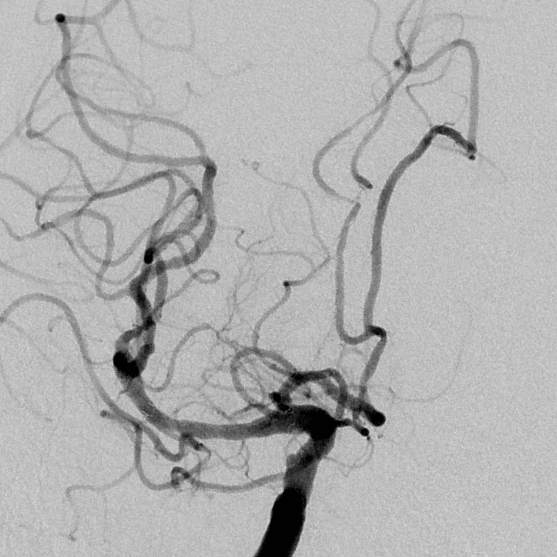

最后,手术顺利进行,术后老人家的狭窄完全消除,缺血改善,消除了进一步脑梗塞的风险……,经过术后5天的观察和修整,一切顺利,老人家明天就要出院回家过国庆节啦!